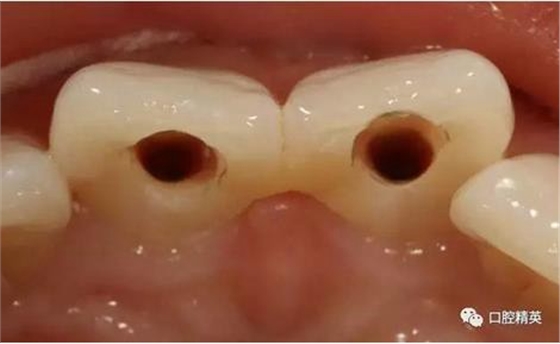

(五診)去除臨時(shí)冠,澤康全瓷冠戴入,調(diào)合,粘接。

齲洞低已近髓

修復(fù)體展示

修復(fù)體戴入